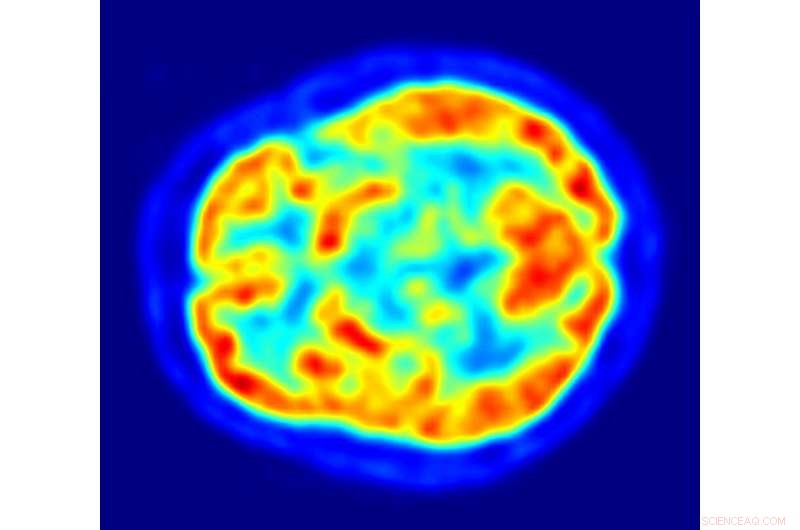

A PET scan of the human brain showing energy consumption. The brain consumes seven times less power than a typical laptop but is capable of far more complex tasks. Credit: Jens Maus, Wikimedia Commons

Remarkably, predictions made by fairly crude models are turning out to describe the brain's circuits rather well, often challenging traditional thinking. In general, Balasubramanian's calculations suggest that animals have evolved to get the biggest cognitive bang for the least possible number of neurons. "Neurons are expensive!" he says, pointing out that the brain makes up just two per cent of our bodyweight but represents 20 per cent of our metabolic load. The brain consumes just 12W of power, seven times less than a typical laptop computer, yet boasts significantly more computational power harnessed to perform subtler functions. "The brain can make us fall in love, whereas the computer hardly recognizes a face," he says.